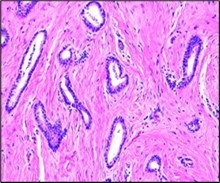

Ultrastructural examination exhibits focal ductal differentiation. Myoepithelial cells and basement membrane are absent 3, 4. Figure 1

Figure 1.Tubular carcinoma delineating tubules layered by cuboidal to columnar epithelial cells impregnated with miniature to intermediate nuclei, apical snouts and surrounding desmoplastic stroma 7.